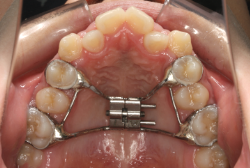

混合歯列期から治療開始した側方拡大による非抜歯症例

そこで、まず急速拡大装置を使用して上顎骨の拡大を行い、上顎骨の容量が拡大したことを確認後、マルチブラケット装置を使って全体の修正をする、と言う二段階の作戦をとることになりました。

急速拡大装置を1日1回装置の中央にある拡大ネジを、ご自身で回して頂くことで25日間くらいかけて、6mmほど拡大しました。拡大後は、上顎の前歯の隙間が広がっていることがお分かりいただけると思うのですが、土台の骨ごと広がるのでこのような隙間ができます。その後1年半くらいマルチブラケット装置を使用して、全体の修正を行いました。

結局、歯の本数を減らすことなく、すべてご自分の歯を残して正しい配列にすることができました。このケースの場合、2009年10月より拡大と経過観察を行い、2012年3月より1年2ヶ月マルチブラケット装置を装着、2013年5月に治療を終了しました。2段階で行う治療としては短期間で終了しているケースと思います。